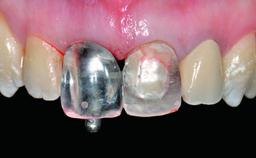

A healthy 28-year-old female patient presented for a consultation on treatment options to restore her upper right central incisor. At the clinical examination, the tooth responded to percussion and palpation. The gingiva was red and slightly swollen, with a mid-facial probing depth of 10 mm. The upper right lateral incisor showed no signs or symptoms, did not respond to exploration and percussion, and the vitality test was positive. The periapical radiograph revealed that tooth 11 had been endodontically treated, with no lesion evident at the apex. A small radiopaque calcified structure surrounded by a narrow radiolucent zone (3 × 3 mm) was present at the apex of tooth 12.

Provisional Implant-Supported Prosthesis Prosthodontic margin > 3 mm apical to mucosal margin Prosthodontic margin > 3 mm apical to mucosal margin